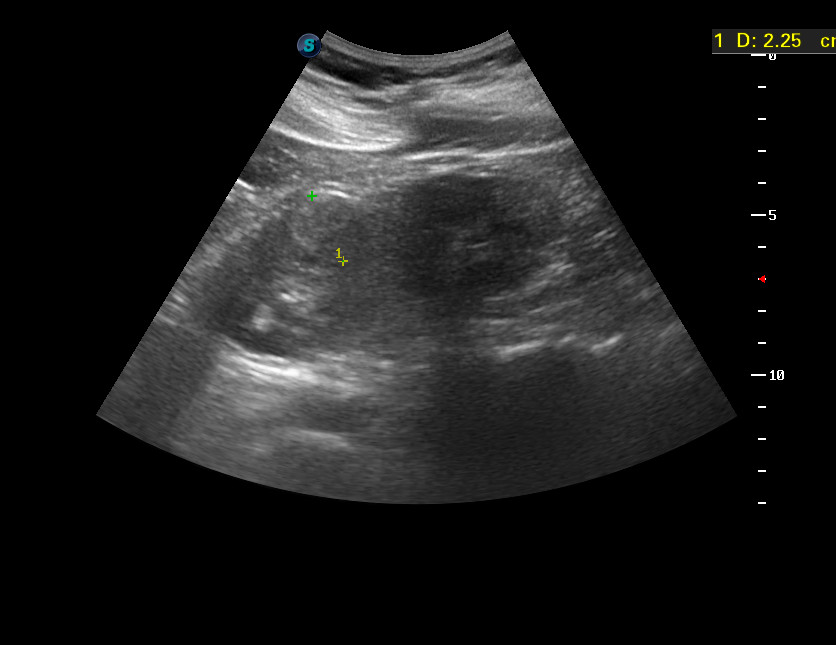

УЗИ, рак почки, малая опухоль. RCC, small tumor, ultrasonography.

Женщина средних лет, жалоб не предъявляет.

Левая почка.